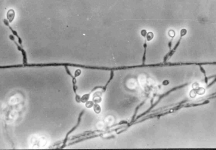

| Species Name: | Scedosporium prolificans |

| Taxonomy: | FUNGI Ascomycota, Sordariomycetes, Microascales, Microascaceae |